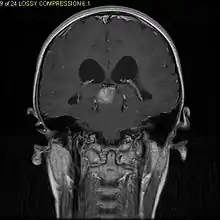

Diagnostic method | MRI, CT scan |

Usually – depending on the interview of the patient and after a clinical exam which includes a neurological exam and an ophthalmological exam – a CT scan and/or an MRI scan will be performed to confirm the presence of a tumor. They are usually easily distinguishable from normal brain structures using these imaging techniques. A special dye may be injected into a vein before these scans to provide contrast and make tumors easier to identify. Pilocytic astrocytomas are typically clearly visible on such scans, but it is often difficult to say based on imaging alone what type of tumor is present.